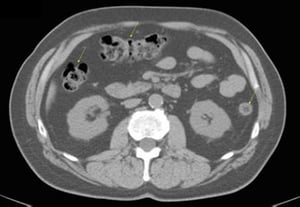

CT-Scan von Abdomen und Becken mit normaler Anatomie ohne Kontrastmittel (Folie 18)

Diese Abbildung zeigt das Jejunum (Pfeile).

© Springer Science+Business Media